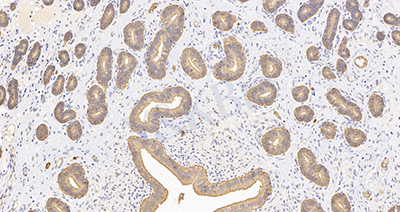

1.Triton X-100 化学名称为聚乙二醇辛基苯基醚,是一种去污剂。在免疫组织化学(10 μm 以上厚切片) 和免疫细胞化学中一般用 Triton X-100 作为细胞通透剂,在膜上打孔。

2.其作用原理:Triton X-100 可以溶解细胞膜、细胞核膜、细胞器膜上的脂质而使抗体及大分子结构的物质进入胞浆和胞核内,故在细胞免疫组化时尤为推荐使用,这样抗体就能顺利进入胞内与相应抗原结合。